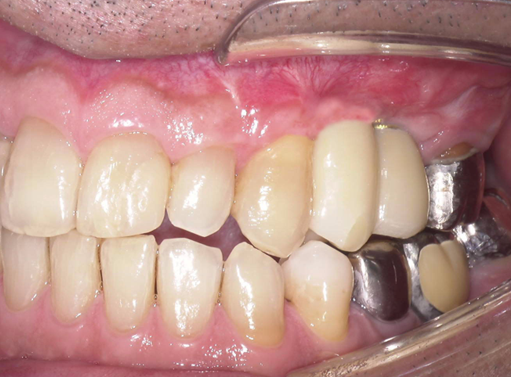

①歯根破折により右上小臼歯が動揺し、歯肉が腫れてしまい、周囲の歯槽骨が吸収していてインプラント埋入

が出来ないと他院で診断され、当院にインプラント治療を希望されました。

予定通りジルコニアクラウンにて、インプラント修復が行えました。